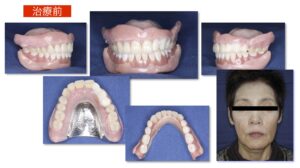

治療前 使用中の上下顎総入れ歯は、修理のつぎはぎ痕が多く存在しています。総入れ歯の土台となるあごの骨の吸収量が多く、また噛み合わせが左にズレていることから、入れ歯が吸着してよく噛めることがは難しい状態でした。

70代女性。今の入れ歯が動いて噛めないとの主訴で来院されました。10年前に現在使用中の上下顎総入れ歯を装着し、何回も調整を繰り返してきたとのこと。数年前から上下ともに入れ歯が動くのが気になるようになり、最近では入れ歯が何度もはずれるようになったため来院しました。うまく食事ができないため「よく食べれるようになりたい」、そして「入れ歯っぽくない自然な見た目」で製作して欲しいとのご要望がありました。

【治療概要】治療用義歯を装着して機能改善を図った上で,最終の上下顎総入れ歯を装着した

【入れ歯の種類】上下顎治療用義歯,上下顎カラーリングBPS総義歯